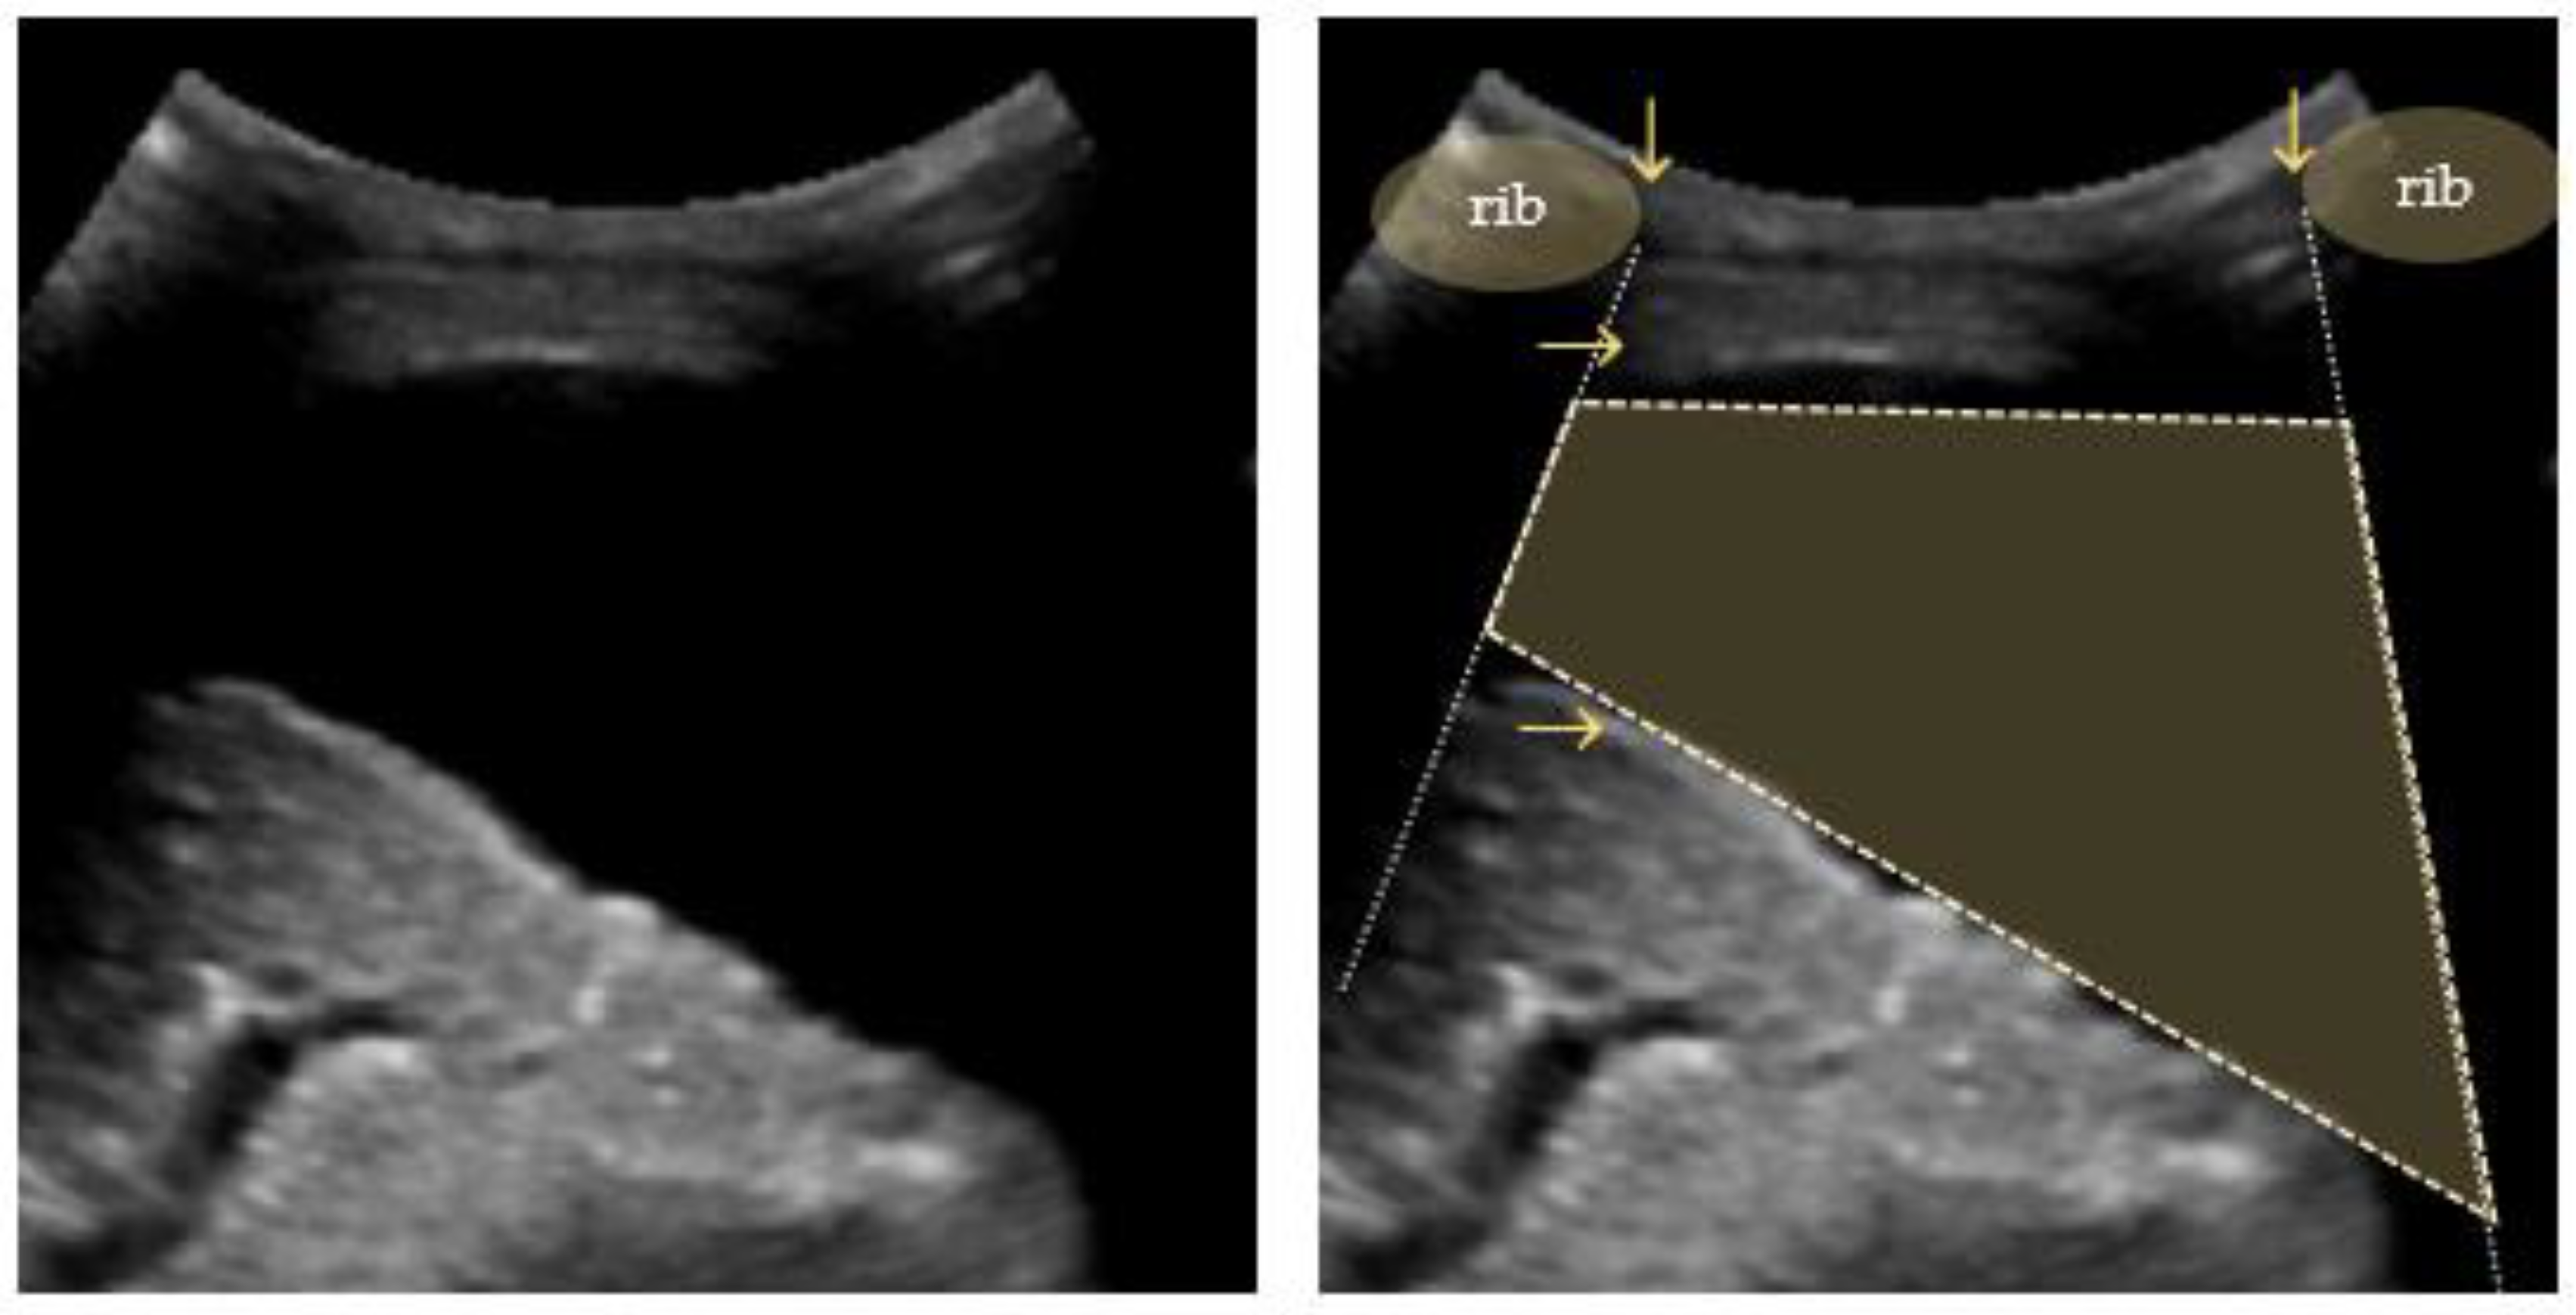

4.4. Pleural Effusion